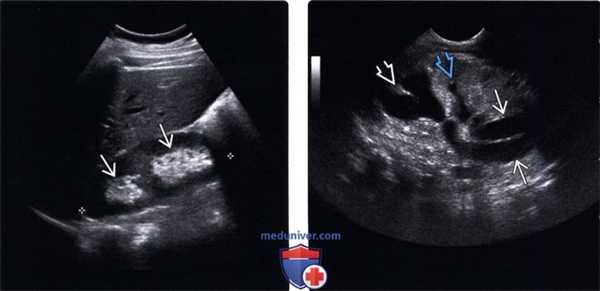

(Левый) На продольном УЗ срезе визуализируется две почечные лоханки, разделенные почечной паренхимой.

(Правый) На продольном УЗ срезе визуализируются выходящий из почки раздвоенный мочеточник. Гидронефроз в верхней половине почки, в нижней половине также наблюдается небольшое расширение, связанное с пузырно-мочеточниковым рефлюксом.